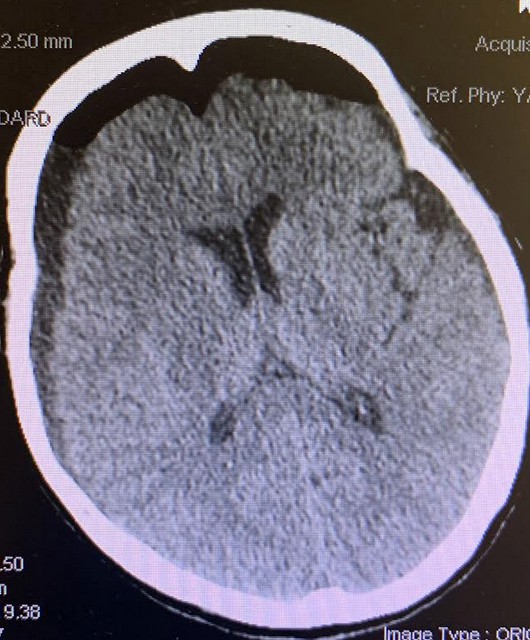

We reported a case of a 77-year-old right-handed female with a history of pre-diabetes, thyroid goiter, osteoporosis, hypertension, hyperlipidemia, transient ischemic attack/stroke on daily aspirin (ASA), presenting with one week of low-grade fever and generalized weakness. Patient had a fall in the bathroom and hit her head, prompting family members to bring the patient to the hospital. Computed tomography of the head (CTH) showed an old lacunar infarct in the right caudate nucleus, large acute on chronic subdural hematoma over the right frontoparietal region measuring up to 20 mm, and midline shift towards the left measuring 9.4 mm (Figure 1). On arrival, the patient was found to have significant sinus tachycardia, and the lab results were significant for urinary tract infection and chronic leukopenia. On exam, patient was awake, alert, oriented, with left facial droop, left drift, left sided weakness 4+/5.

Figure 1. CTH large acute on chronic subdural hematoma over the right frontoparietal region measuring up to 20 mm. Midline shift towards the left measuring 9.4 mm